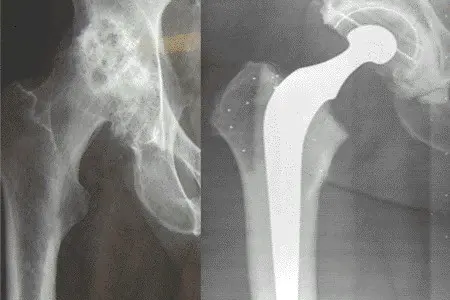

I prinsippet består en hofteprotese av en stamme som går ned i lårbenet, et hode som settes på toppen av stammen som erstatning for lårbenshodet, og en kunstig hofteskål (koppen) (figur 1). Forskjellige stammer kan kombineres med kopper av forskjellige merker, slik at kombinasjonsmulighetene blir svært mange.

Figur 2 viser røntgenbilder av en hofte med artrose (figur 2a til venstre) og en hofte som har fått en sementert hofteprotese (figur 2b til høyre).